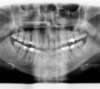

Décalage traité par gouttières

Début de traitement